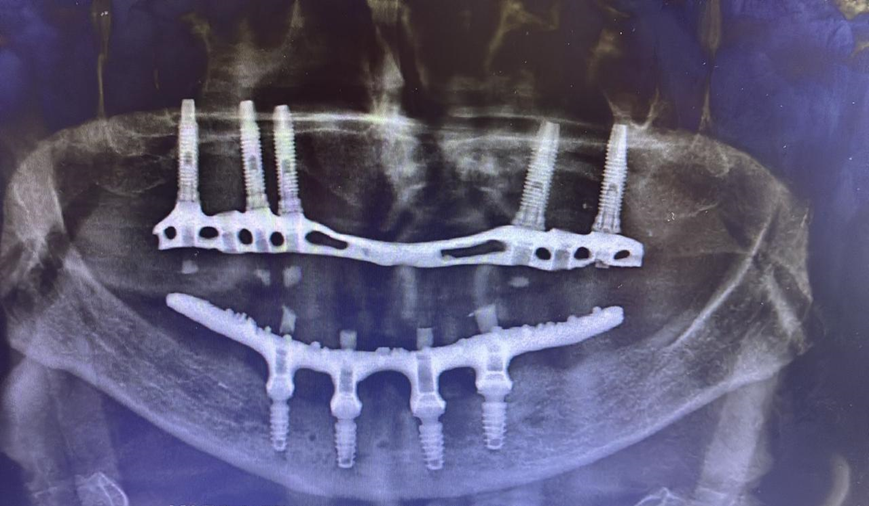

Paciente de 62 anos, do sexo feminino, sem comorbidades e história médica pregressa, apresentava severa reabsorção óssea em regiões anteriores e posteriores da mandíbula devido a uma peri-implantite (Figuras 1A e 1B). Feita a remoção dos implantes, a paciente optou por utilizar uma prótese total mucossuportada até a nova intervenção com prótese do tipo protocolo inferior. Após seis meses, a mandíbula encontrava-se cicatrizada (Figura 2). Como parte do protocolo diagnóstico, foi realizada tomografia computadorizada pela técnica do duplo DICOM. Com a severa perda óssea em região anterior de mandíbula, optamos por realizar a cirurgia de forma guiada, aumentando a previsibilidade e precisão da cirurgia. Os arquivos obtidos foram exportados para o software CoDiagnostiX, possibilitando a realização do planejamento reverso e o subsequente posicionamento virtual dos implantes (Figura 3). Com base no planejamento, optou-se pela instalação de quatro implantes Implacil Osstem CM AR Due Cone (3,5 x 7 mm), associados a mini-cônicos de 1,5 mm (Figuras 4A, 4B, 4C, 4D e 4E). A partir da tomografia da prótese da própria paciente, confeccionaram-se duas guias cirúrgicas: uma guia de pino de fixação (Figura 5) e uma guia de fresagem para a instalação dos implantes (Figura 6). Durante o procedimento cirúrgico, inicialmente foi posicionada a guia de pino de fixação para fresagem dos pinos de fixação e orientação da sequência cirúrgica (Figura 7). Após essa etapa, a guia foi substituída pela guia de fresagem dos implantes (Figura 8), utilizada para a fresagem e inserção dos implantes planejados (Figura 9). Concluída a instalação, optou-se por seguir o fluxo analógico, com a adaptação dos mini-cônicos 1.5 mm (Figura 10), realização da transferência de moldagem com silicona de adição leve e sutura com fio absorvível Vycril 6-0. O guia inicial foi adaptado com broca Maxicut, possibilitando sua utilização como molde de orientação para o laboratório protético (Figura 11). Após a moldagem, foram posicionadas as tampas de proteção sobre os implantes. Na fase protética, transcorridas 48 horas do procedimento cirúrgico, foi realizada a prova clínica da barra metálica e dos dentes (Figura 12). Na etapa subsequente, 72 horas após a cirurgia, procedeu-se à instalação e entrega do protocolo mandibular inferior e radiografia prévia, reabilitando funcional e esteticamente a paciente em curto espaço de tempo (Figuras 13A e 13B).